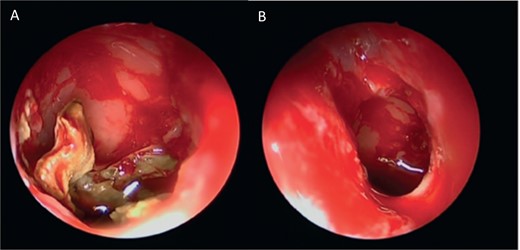

Intra-operative endoscopic view (A) right middle meatal antrostomy showing fungal debris, (B) clean right maxillary sinus after removal of the debris.

A 30-year-old lady presented to the clinic with a complaint of right facial pain, recurrent rhinorrhea with post-nasal discharge, nasal endoscopic examination was unremarkable. A non-contrast computed-tomography scan (NCCT) of the paranasal sinuses (Fig. 1) was suggestive of isolated right fungal maxillary fungal ball (FB). The patient underwent endoscopic sinus surgery (ESS) with (Fig. 2) right middle meatal antrostomy and removal of fungal debris. The patient was followed up regularly and remained symptom free.